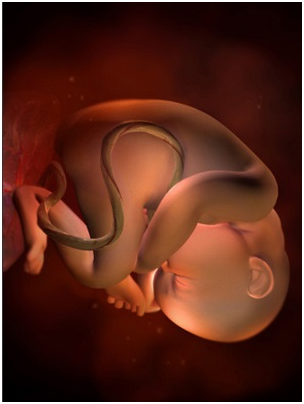

怀孕第34周此时胎儿已经为分娩做好了准备,将身体转为头朝下的姿势。你最近会感觉有一点儿累,这...

怀孕第34周此时胎儿已经为分娩做好了准备,将身体转为头朝下的姿势。你最近会感觉有一点儿累,这... -

怀孕第35周离分娩期越来越近,你可能会有些忐忑不安,甚至是紧张,和丈夫、朋友或自己的妈妈多聊...

怀孕第35周离分娩期越来越近,你可能会有些忐忑不安,甚至是紧张,和丈夫、朋友或自己的妈妈多聊... -

怀孕第36周这时你要多了解一些有关临产征兆的知识,了解什么是宫缩、见红、破水,遇到这些意外该...

怀孕第36周这时你要多了解一些有关临产征兆的知识,了解什么是宫缩、见红、破水,遇到这些意外该... -

怀孕第37周这段时间,你要每周体检一次了。现在宫缩可能出现得更为频繁,如果发现有出血现象,应...

怀孕第37周这段时间,你要每周体检一次了。现在宫缩可能出现得更为频繁,如果发现有出血现象,应... -

怀孕第38周恭喜准妈妈,从现开始你的宝宝已经是足月儿了,随时可能出来和你见面哦!你现在是不是...

怀孕第38周恭喜准妈妈,从现开始你的宝宝已经是足月儿了,随时可能出来和你见面哦!你现在是不是... -

怀孕第39周你的小宝宝现在已经准备好向这个世界报到了,准备好了吗,年轻的爸爸妈妈?也许明天?...

怀孕第39周你的小宝宝现在已经准备好向这个世界报到了,准备好了吗,年轻的爸爸妈妈?也许明天?... -

怀孕第40周你是否觉得等待的日子格外漫长?备战状态的气氛有些紧张?不妨和老公一起听听音乐,看...

怀孕第40周你是否觉得等待的日子格外漫长?备战状态的气氛有些紧张?不妨和老公一起听听音乐,看... -